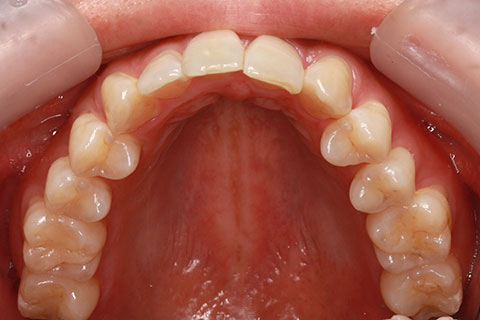

ハーフリンガル矯正3:上の歯のみ舌側矯正で治療(矯正期間24ヶ月)

治療前

治療中(開始直後)

治療中(開始半年後)

治療後

- 年齢・性別

- 25歳女性

- 治療期間

- 2年0ヶ月

- 抜歯

- 上下4番抜歯

- 治療費

- 110万円

- 治療内容

- 施術の副作用(リスク)

- 表側矯正と比較して、力学的な操作性が複雑なため、ボーイングエフェクトを起こしやすい。